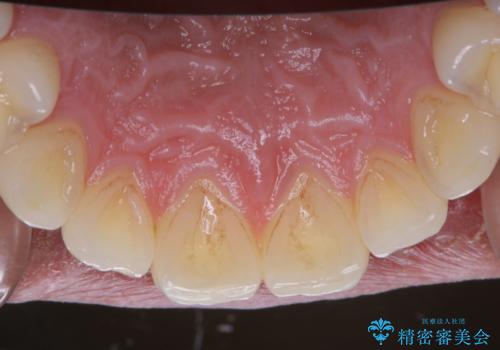

全体的に汚れが付着していたため、まずはPMTCでご自身の本来の歯の状態にしてから、ホワイトニングにいついて考えましょうとなりました。

PMTCでは専門的な機械や材料を使用して、徹底的に汚れを除去するため、虫歯・歯周病・口臭予防などにつながります。

また、ホワイトニングを考えている場合も、まずはPMTCで汚れの除去を行って判断することをおすすめします。